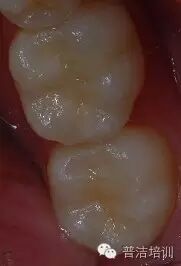

【前后对比】

术前

术后